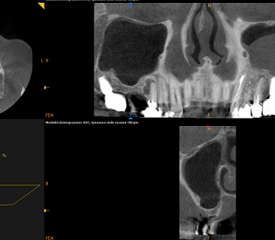

Rialzo del Seno Mascellare

Rialzo Seno Mascellare